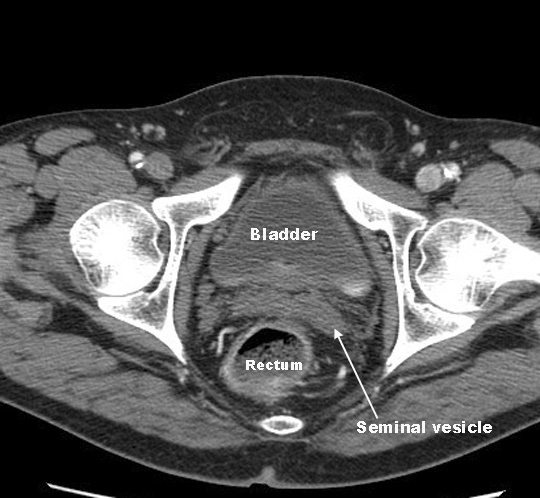

- Relationship

- Posterior

- Sacrum

- Anterior

- Male